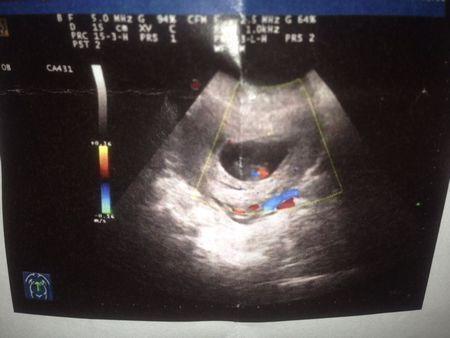

心脏点状强回声是B超时最常见的,虽然这种强回声并不代表胎儿存在心脏问题,但是也提示了宝宝出生后,出现染色体异常的风险。一般来说,有心脏点状强回声的胎儿比没有点状强回声的宝宝染色体异常的风险要高5-10倍左右。特别是高龄产妇,出现胎儿染色体单倍体异常的风险更高。心脏点状强回声多发生于左心室,通常直径1-6mm,可以单发,也可以多发。中期妊娠声像图上显示心室内强回声点的发生率约为2.1%-5%。如果检测到心脏点状强回声的情况,一般医生也是会建议复查,复查时点状没有消失的话会建议做无创DNA检测或者是脐带血穿刺。